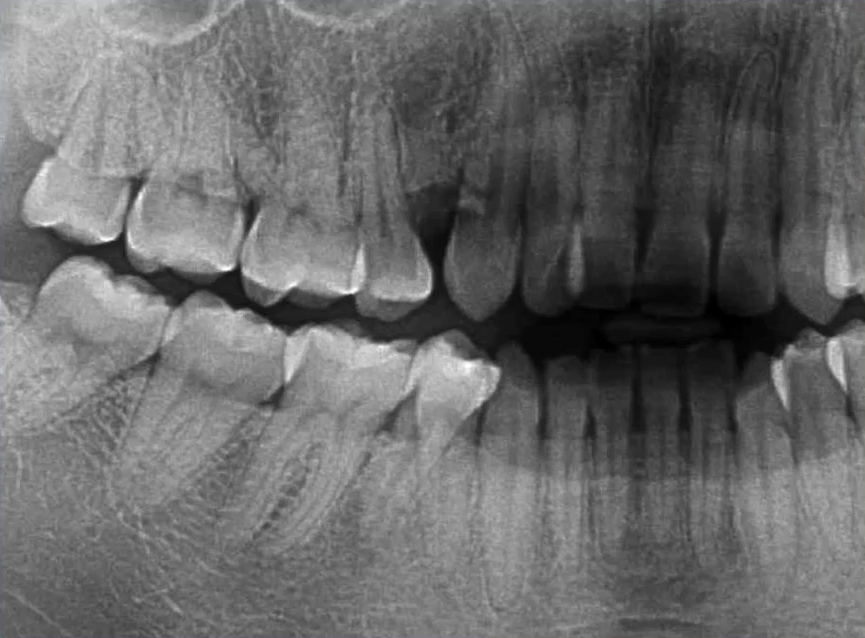

1. 全面显示牙列:牙体疾病初步诊断

比如下面这张片子显示出的龋坏合并根尖周炎。

2. 混合牙列期:乳牙情况、恒牙胚观察

因为曲面断层片反映的是上下颌牙齿、上颌窦、关节,在一张片子中所展示的解剖结构较多。比如刚才的片子,最容易诊断的是右下6远中邻面深龋合并根尖周炎,左下有埋伏的多生智齿,右侧是垂直智齿。